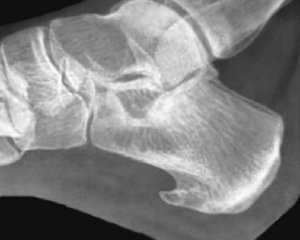

Что это такое и почему возникает? Пяточная шпора — это костный нарост, который формируется в результате воспалительных процессов в фасции, соединительных тканях стопы.

В большинстве случаев для установления диагноза пяточной шпоры требуется использование инструментальных методов исследования. Рентгенография стоп помогает обнаружить наличие костного нароста, его размеры и другие проблемные зоны в стопе.

Если рентгенографические данные недостаточны для подтверждения диагноза, можно прибегнуть к магнитно-резонансной томографии (МРТ). Этот метод позволяет детально рассмотреть не только костную структуру стопы, но и мягкие соединительные ткани, что дает возможность выявить множество проблем на ранних стадиях.